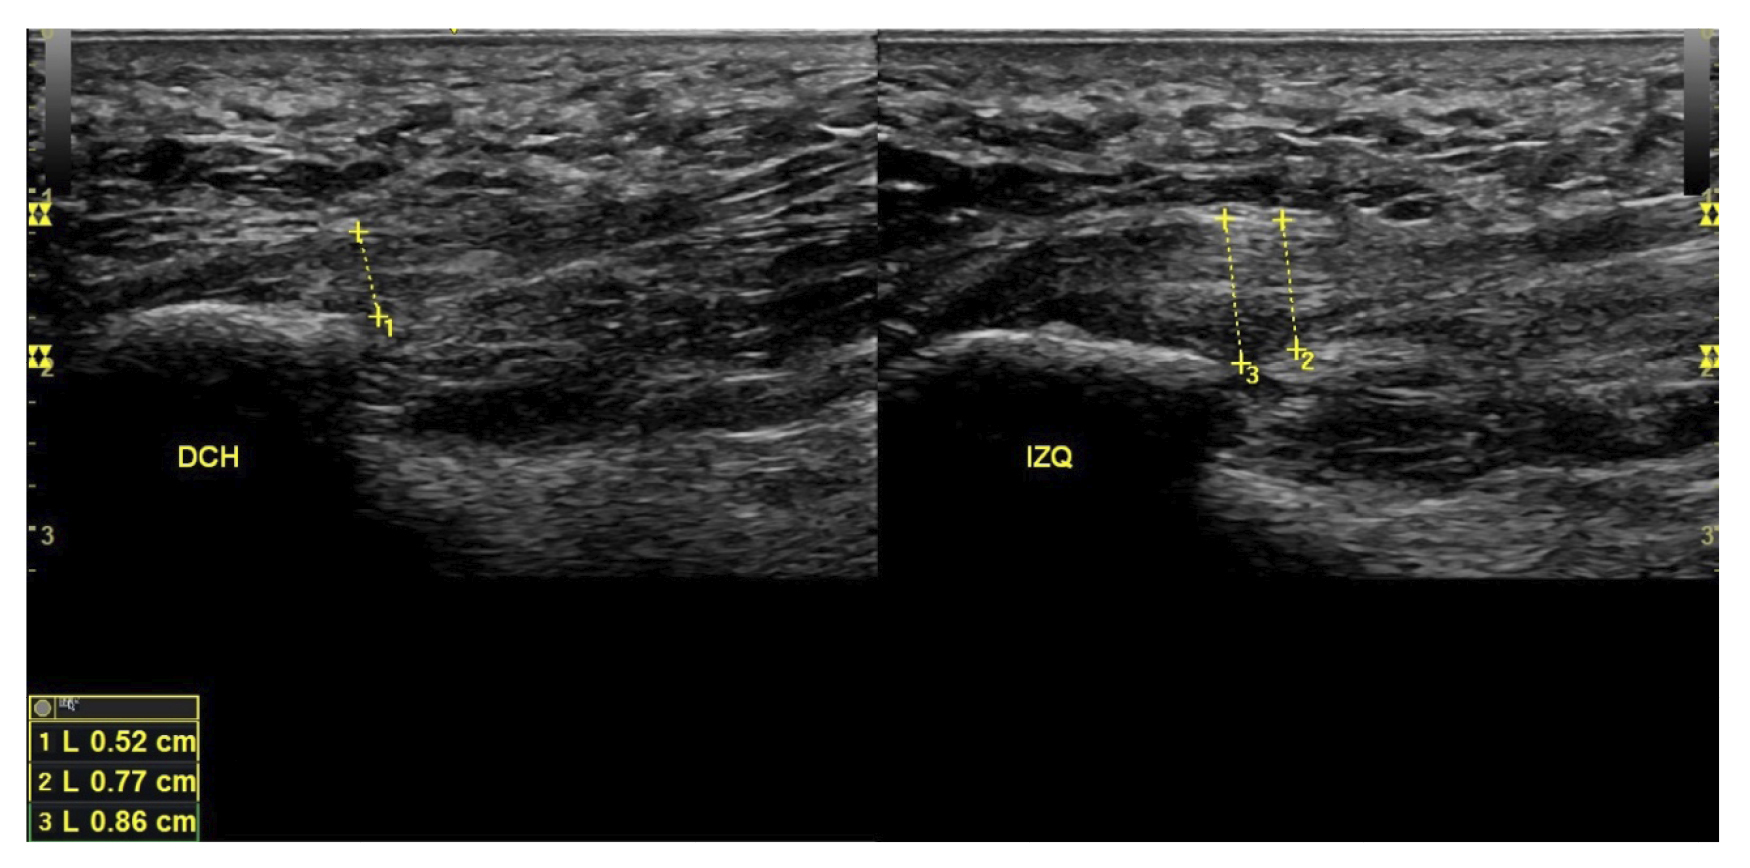

A todos los pacientes se les realizó una evaluación clínica y una evaluación ecográfica. La evaluación clínica se basó en una escala analógica visual (EVA) (13) (0-10) y el índice de función del pie (FFI) (14,15), que evalúa la función en una escala de 0 a 100. También se clasificó a los sujetos como sedentarios, activos o deportistas en función a su actividad física diaria, así como si era la primera vez que aparecía la enfermedad, era una recidiva o era crónica(16). También se evaluó el sexo, el peso y la talla, la presencia de vascularización en la fascia plantar visualizada con ecografía en el momento de la evaluación inicial y la forma biconvexa(17) o aplanada de la fascia plantar (Figura 1).

Figura 1. Fascia plantar con morfología normal a la izquierda y fascia plantar con morfología biconvexa a la derecha.

El diagnóstico se estableció en base a los síntomas y se confirmó mediante ecografía con equipo de alta resolución (Alpinion Ecube 9, ALPINION MEDICAL SYSTEMS Co., Ltd., República de Korea) con transductor lineal de 6 a 12 MHz (Figuras 2 y 3).

Figura 3. Área de medición del grosor de la fascia plantar. La línea punteada corresponde con la medición del grosor.